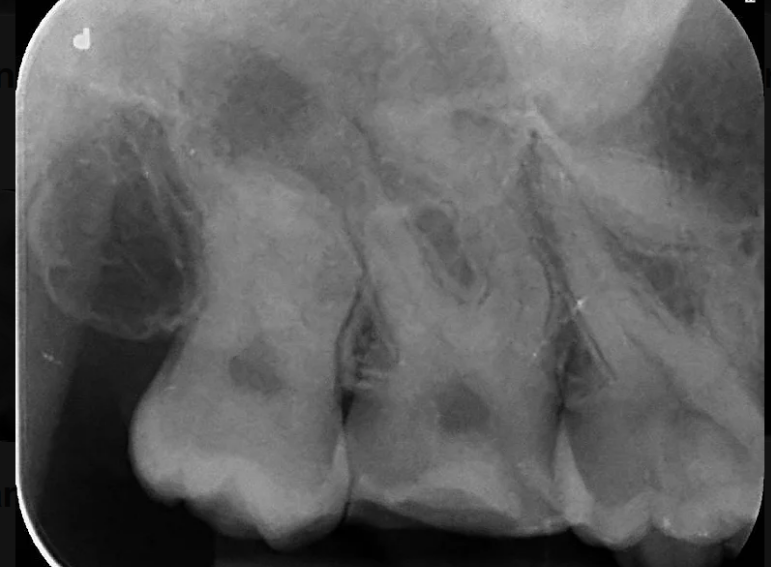

Separated instrument management on a sclerosed upper second molar.